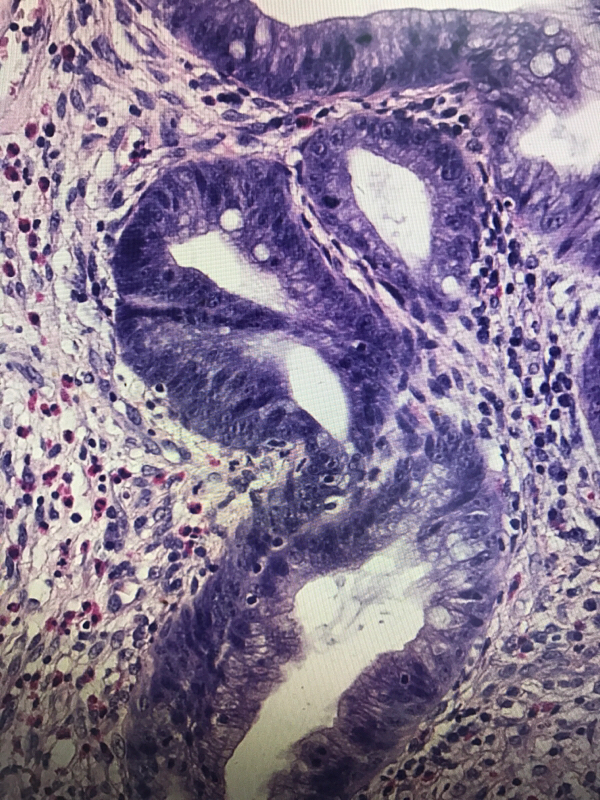

直肠息肉

一般病史

血便4天

灰红结节一枚,大小1✖️0.6✖️0.6cm,切面灰红,质软

管状腺瘤,低级别还是高级别?

幼年性息肉,灶性低级别

幼年性息肉?

幼年性息肉